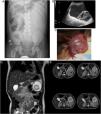

(A–C) Radiological and surgical findings in case A. (A) Abdominal X-ray with the patient in the supine position revealing a mass effect in the left abdomen with displacement of intestinal loops toward the right abdomen. No signs of bowel obstruction. (B) High-resolution grayscale ultrasound image revealing a cystic lesion with echogenic contents, internal septa and another pseudosolid lesion within. (C) Intraoperative image revealing a very large (15×9×3cm) multicystic mass pink in color. (D and E) Radiological findings in case B. Multiphasic contrast-enhanced MRI images in the coronal (D) and axial (E) planes following intravenous administration of gadolinium. Round lesion measuring approximately 5.3cm along all 3 axes located in the left hypochondrium with contents of probable hemorrhagic origin demarcated by a hypointense shape of a capsule or pseudocapsule. No evidence of organ dependence, edema or infiltration of adjacent structures.

Case ABoy aged 3 years with an unremarkable previous history that sought care in the emergency department for diffuse abdominal pain of 3 days’ duration that exhibited guarding on palpation of the left side of the abdomen. He had been assessed 1 week prior due to a similar episode associated with fever and vomiting that had been managed with conservative treatment. The abdominal X-ray revealed a mass effect in the left side of the abdomen, and the abdominal ultrasound the presence of a large intraabdominal cystic lesion (Fig. 1A and B). As his condition was deteriorating, the patient underwent an exploratory laparotomy that revealed extensive cystic tumor dependent on the omentum and anchored to the greater curvature of the stomach, which was completely resected (Fig. 1C). The findings of the gross and histological examination led to diagnosis of lymphangioma with haematic content.

Girl aged 4 years assessed in the emergency department for colicky abdominal pain of 5 day's duration associated with vomiting. The patient had had similar episodes before that had resolved satisfactorily with enemas. She underwent an ultrasound examination that revealed a very larger multicystic lesion in the left hypochondrium. In this case, the patient was clinically stable, which allowed performance of a magnetic nuclear imaging (MRI) scan to complete the investigation and schedule surgery. The scan revealed a cystic lesion at the level of the mesentery in close contact with the tail of the pancreas (Fig. 1D and E). The patient underwent laparoscopic-assisted resection of the lesion with bowel anastomosis. The pathology report described a benign cystic vascular lesion with immunohistochemical features compatible with lymphangioma (Table 1).